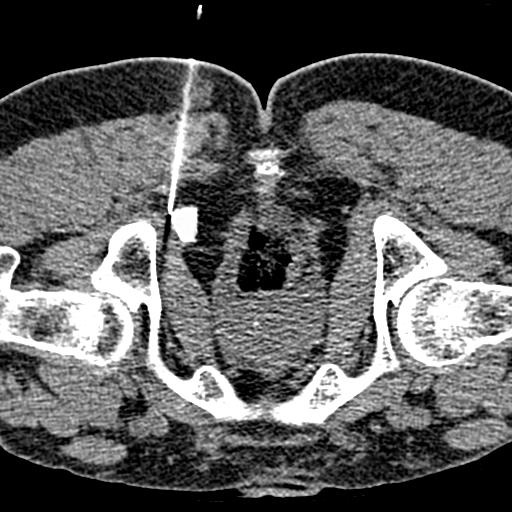

Ich leide auch an einer Pudendusneuralgie. Ist die vom Schmerz betroffene Region lokalisiert und kann Sie eindeutig einem Rückenmarksnerven zugeordnet werden dann gilt es durch ein Bildverfahren MRT CT festzustellen was die Ursache des Wurzelkompressions-Syndroms ist. Eine Pudendusneuralgie wird idR.

Ist die vom Schmerz betroffene Region lokalisiert und kann Sie eindeutig einem Rückenmarksnerven zugeordnet werden dann gilt es durch ein Bildverfahren MRT CT festzustellen was die Ursache des Wurzelkompressions-Syndroms ist. Leider hat die erste Behandlung nichts gebraucht sodass ich ein zweites Mal hinfahren muss. Verursacht werden die Schmerzen hauptsächlich durch Kompression des Pudendusnervs im Pudendus-. Seit 2 Monaten suche ich nach einem Befund. Ist die vom Schmerz betroffene Region lokalisiert und kann Sie eindeutig einem Rückenmarksnerven zugeordnet werden dann gilt es durch ein Bildverfahren MRT CT festzustellen was die Ursache des Wurzelkompressions-Syndroms ist. Daher wird eine Nervus Pudendus Neuralgie auch gerne als Alcock-Syndrom bezeichnet. Die Abteilung für Neuro-Urologie hat sich auf die Diagnose und Therapie der Pudendus-Neuralgie spezialisiert. Anzeige Oft nähmen die Schmerzen beim Radfahren oder im Sitzen zu. Die Pudendusneuralgie Pudendus-Neuralgie ist eine seltene Erkrankung die mit blitzartigen Schmerzen im Bereich zwischen Genital und After einhergeht.